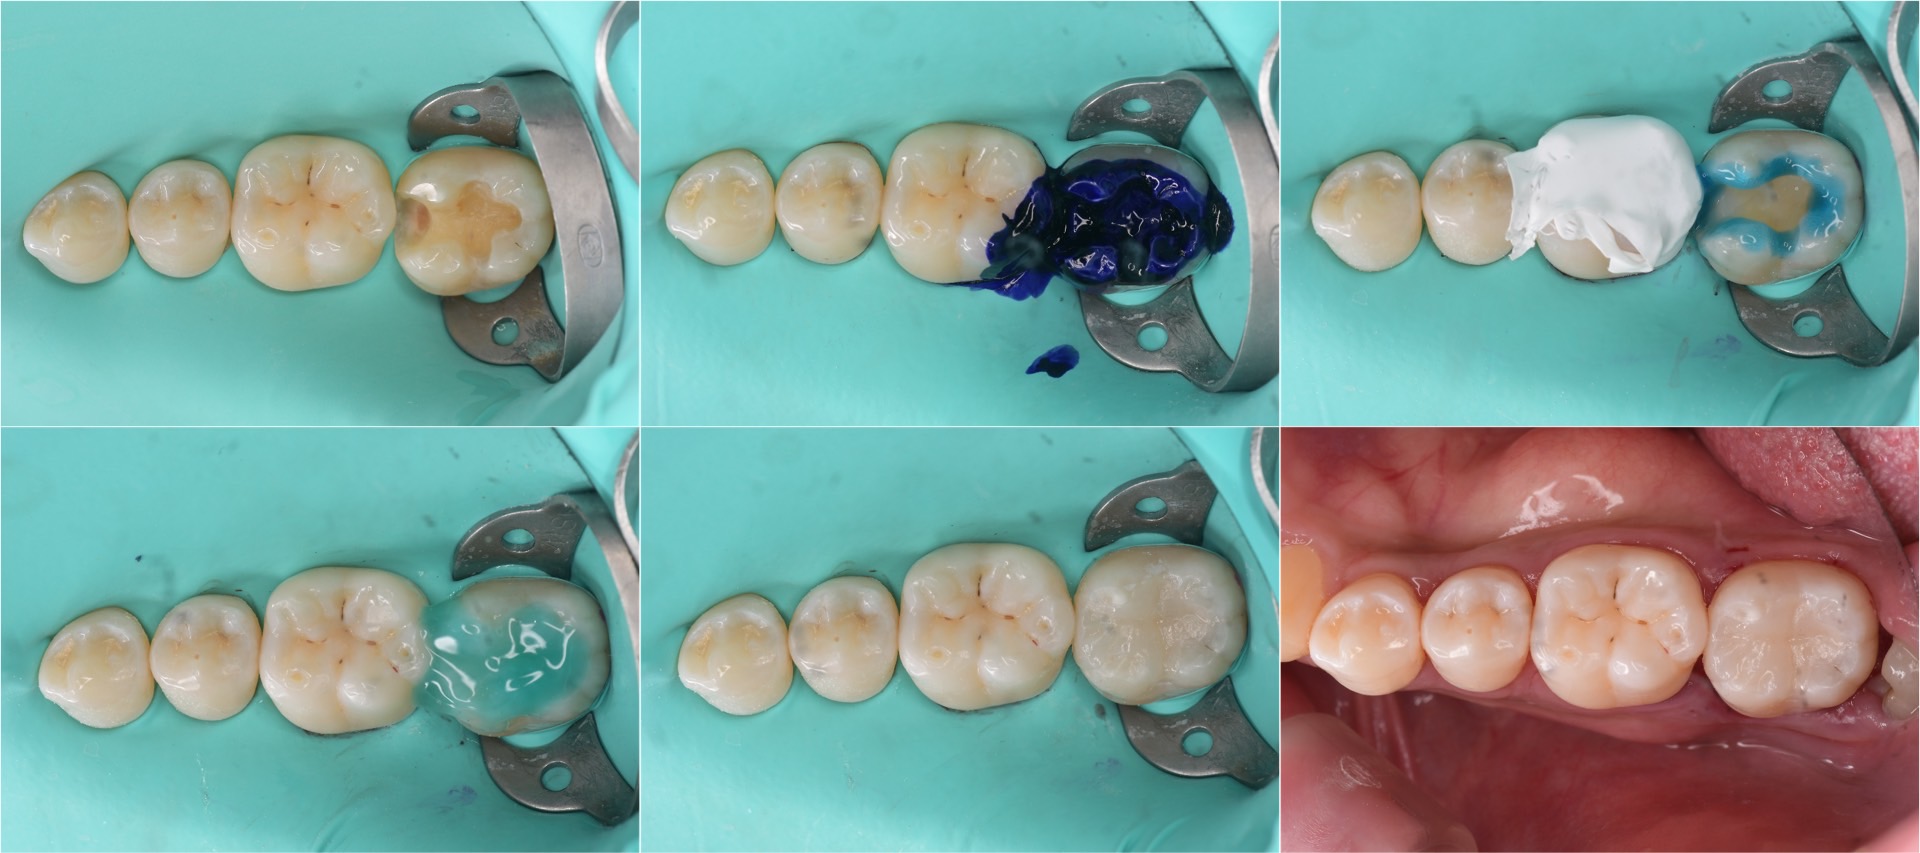

治療の様子

治療の最中から唾液などによって細菌感染することの無いよう、またしっかりとした接着操作のためなどのため、「ラバーダム防湿」を行ったうえで治療しています。